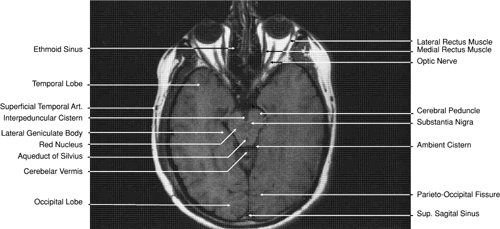

The globe is shown in Figure 12. The orbit and periorbital structures are shown in Figures 13 through 16, and the optic canal is shown in Figures 17 through 26. The cavernous sinus and optic chiasm are shown in Figures 27 and 28, and the posterior visual pathway and cranial nerves are shown in Figures 29 through 33.

Fig. 31. Axial T1-weighted image through the cerebral peduncle at the level of oculomotor nerve.

Fig. 32. A. Axial computed tomography soft tissue image at the level of suprasellar cistern. B. Axial computed tomography soft tissue image at the level of thalamus. C. Axial T1-weighted image at the level of thalamus.